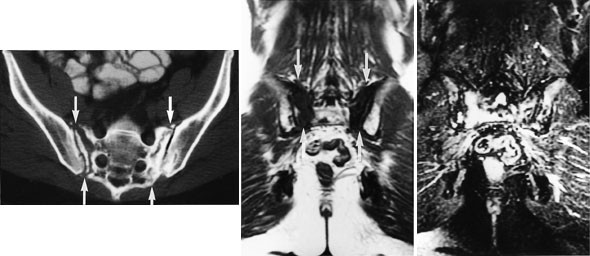

Cancer cervicis uteri

Tumor fremstilles tydelig på T2-vektede bilder (fig 12). Størrelsen er den viktigste faktor for prognosen, og MR gir god informasjon om denne (15). MR kan dertil påvise infiltrasjon til parametrier, bekkenvegg, blære og rectum samt affeksjon av urinledere. Siden den kliniske stadieinndelingen er usikker, har MR stor betydning i primærutredningen, spesielt ved store svulster.